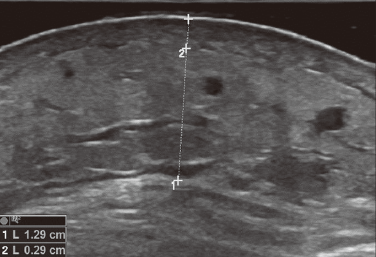

高频超声辅助评估丹毒治疗效果的前瞻性对照研究

靳诗颖 史进军 高启 陈梅 董正邦 严翘 李基健 王飞

摘要 ( 682) PDF (6664 KB) ( 13)

2023, Vol.56(5): 434–438   doi: 10.35541/cjd.20220337